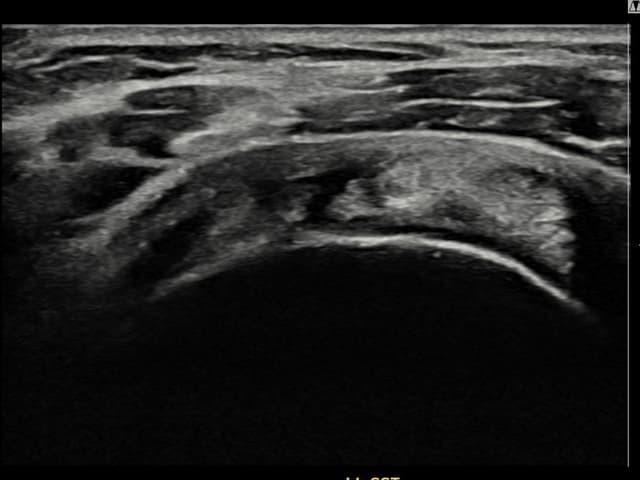

[촬영시기:21.09.27~21.10.07]

[석회분쇄흡입술] 우측 어깨의 야간 통증과 운동 제한으로 수개월간 고통받다 내원한 50세 남성 환자로, X-ray에서 극상근건 내 석회 침착이 확인되어 석회분쇄흡입술을 시행하였습니다.